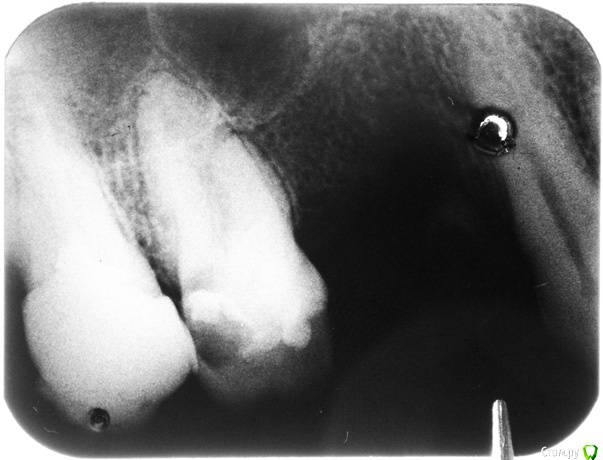

Анбо Опубликовано 15 февраля, 2017 Автор Поделиться Опубликовано 15 февраля, 2017 (изменено) ОПТГ нет. Сходил к другому врачу. Сказала, что снимок плохой (темный), но тоже увидела кариес корня и кисту. Вряд ли они сговорились. Но они зато видели снимок «живьем». Может плохой снимок + потеря качества при перефотографировании привели к тому, что на приведенном здесь фото что-то теряется? Вот поиграл светом-тенью – может что-то проявилось? Это не то, что стрелочками обозначил? Но она была не столь категорична по поводу удаления («Лучше удалить, но можно пока оставить. Но все равно через некоторое время все вернется»). И сказала, что если зуб вскрывать, то будет еще хуже. Мне сделали разрез, чтобы выпустить гной, и назначили азитромицин. Прокомментируйте, пожалуйста.Если на снимке не все видно, укажите, пожалуйста, какие части наиболее важны, я могу в фотошопе сделать их наиболее контрастными. Гистологическое исследование, о котором писал red_butler, не везде делают? Оно имеет какое-нибудь более конкретное название? Изменено 15 февраля, 2017 пользователем Анбо Ссылка на комментарий

Гарриевич Опубликовано 15 февраля, 2017 Поделиться Опубликовано 15 февраля, 2017 это дно верхнечелюстной пазухи"кисты" не видать 5 Ссылка на комментарий

DmitrySH Опубликовано 16 февраля, 2017 Поделиться Опубликовано 16 февраля, 2017 Если у Вас еще сохранились сомнения, то сделайте КТ , все будет понятно. Никакой кисты, просто бухта гайморовой пазухи. 1 Ссылка на комментарий

Bier Опубликовано 16 февраля, 2017 Поделиться Опубликовано 16 февраля, 2017 там четко есть гранулема на медиальном корне. Может ее и назвали "кистой"?? 2 Ссылка на комментарий